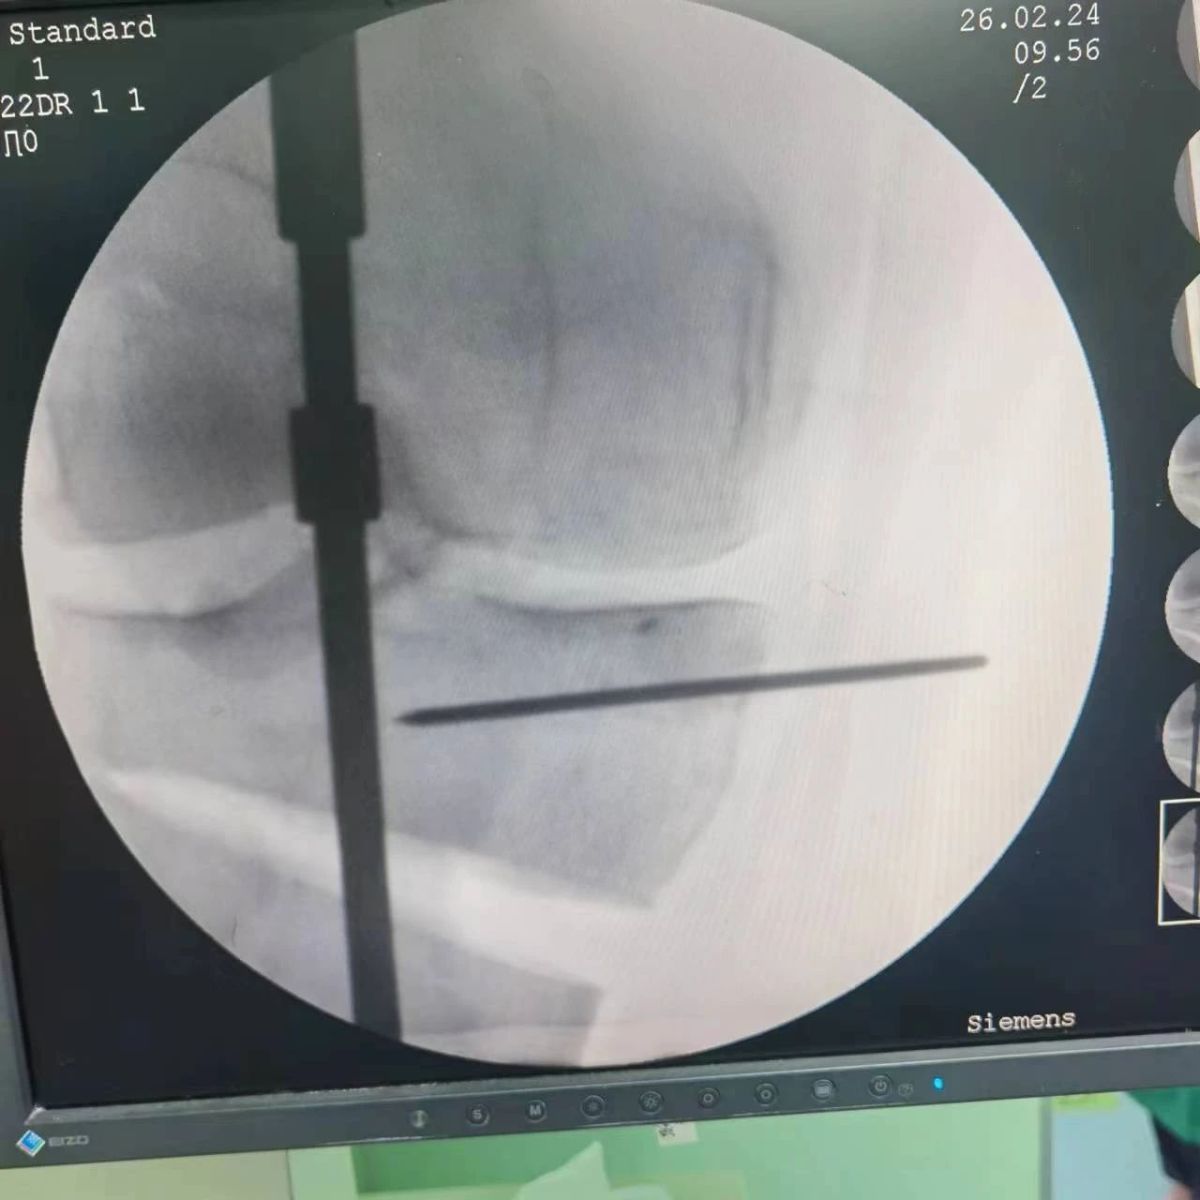

2月26日,漯河市骨科醫(yī)院(漯河醫(yī)專二附院、漯河市立醫(yī)院)膝關(guān)節(jié)外科、運動損傷科(骨六科)在保膝治療方面取得了新的突破,李付彬主任帶領(lǐng)岳龍等團隊醫(yī)師,順利完成“計算機精準(zhǔn)術(shù)前規(guī)劃聯(lián)合3D打印截骨導(dǎo)板輔助脛骨高位截骨治療膝關(guān)節(jié)骨性關(guān)節(jié)炎”的手術(shù),這在漯河市尚屬首例!

患者為一名45歲男性,查體及X片可見明顯的膝內(nèi)翻,內(nèi)翻畸形主要來源于脛骨近端,關(guān)節(jié)鏡下可見內(nèi)側(cè)間室軟骨全層磨損,疼痛較重,年紀(jì)輕輕幾乎喪失工作能力。對于這種日?;顒有枨蟊容^大的患者朋友,我們盡最大可能給予保膝治療,李付彬主任給患者詳細講解了保膝治療的方案(脛骨近端高位截骨)及預(yù)期效果,給患者帶來了極大希望。為了更精確、更微創(chuàng)的治療,李付彬主任團隊緊跟國內(nèi)外科技前沿,采用計算機精準(zhǔn)術(shù)前規(guī)劃,并設(shè)計3D打印截骨導(dǎo)板,力求給患者帶來更精準(zhǔn)、更安全的手術(shù)效果。

李付彬主任團隊通過精準(zhǔn)術(shù)前規(guī)劃,設(shè)計目標(biāo)力線及調(diào)整撐開角度,轉(zhuǎn)化成需要撐開的高度,最終設(shè)計出同等高度的填充塊,術(shù)中驗證力線調(diào)整與術(shù)前規(guī)劃完全一致!

鋼板位置、螺釘位置及長度均可通過術(shù)前規(guī)劃計算,術(shù)中通過定位操作,基本與術(shù)前規(guī)劃一致,手術(shù)快速高效完成,外側(cè)合頁保留完整。無任何并發(fā)癥出現(xiàn)。術(shù)后見鋼板位置及力線糾正近乎完美!

OWHTO手術(shù)效果依賴于多個數(shù)據(jù)參數(shù),比如:截骨的入點、合頁位置的選擇、截骨線的深度、截骨線的方向、撐開的距離等,依托計算機術(shù)前精準(zhǔn)規(guī)劃和3D打印導(dǎo)板可輔助醫(yī)生精準(zhǔn)控制上述參數(shù),使截骨更準(zhǔn)確,真正達到精確的力線調(diào)整,減少術(shù)中透視次數(shù),縮短手術(shù)時間并降低手術(shù)風(fēng)險,從而使得OWHTO得到更好的應(yīng)用,造福患者。